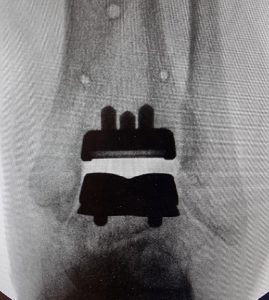

Total Ankle Replacement (TAR) is a surgical procedure to treat advanced stage of ankle arthritis. In this operation, the bones forming the ankle joint are cut and replaced with an artificial joint (prosthesis). The ankle replacement is made up of three parts, Two metallic parts and a plastic insert between the metallic parts. The metallic parts are designed to integrate into the bones and the plastic insert gives a smooth surface for the joint to glide and rotate.

Routinely, a thigh tourniquet (device to stop bleeding) is used to stop blood flow to the ankle during surgery. The ankle joint is approached through a cut made on the front of the ankle. The surgery is performed using specialist equipment and x-rays, the arthritic part of the ankle joint is removed and new joint (prosthesis) is inserted. The operation takes about 2 to 3 hours.

The patient is placed in a plaster splint (back slab) immediately after the operation. Patients are asked not to put any weight through the operated leg for 2 to 3 weeks following surgery. As there is risk of blood clots, patients will be prescribed blood thinning injections post-operatively. Patients are brought back to clinic after 2 weeks, stiches removed and a walker boot is given, patients will progress to full weight bearing by 6 to 8 weeks. X-rays will also be done regularly to check the position of the prosthesis. Physiotherapy input may also be needed, the Doctor will discuss this with you if required